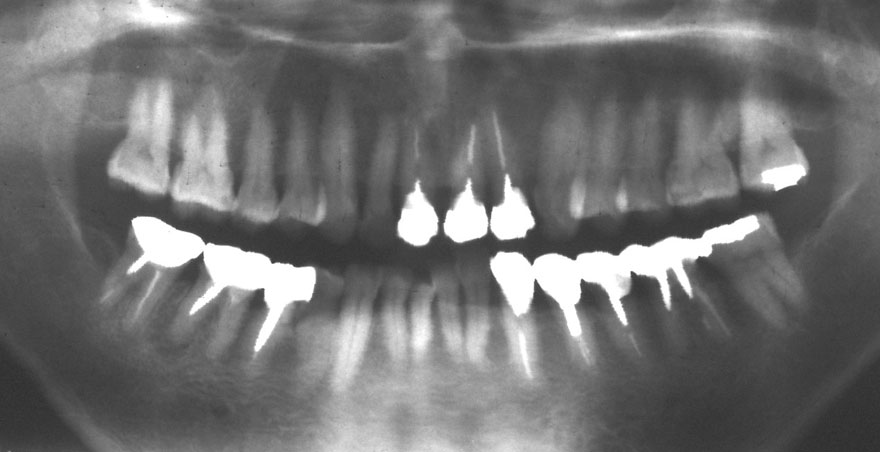

初診時 40歳 女性 平均歯槽骨喪失量:5.24mm

20年後 60歳

平均歯槽骨喪失量:5.79mm

21年間喪失量:-0.55mm

年間喪失速度:-0.027mm

(ケア頻度:1.23ヵ月ごと)